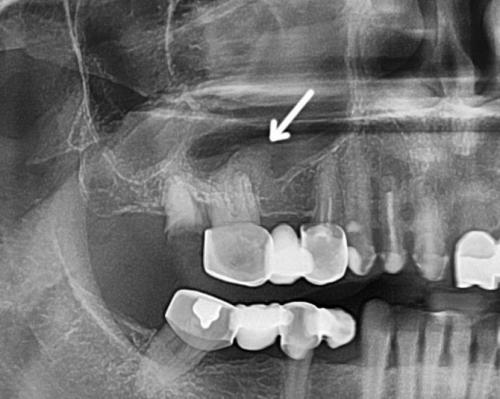

Толщина этой прослойки у разных людей разная — у одних это внушительная пластинка костного вещества, у других этого слоя вовсе нет, а корни верхних зубов расположены непосредственно в пазухе.

Этиологически и патогенетически возникновение хронического одонтогенного гайморита обусловлено распространением возбудителей со стороны инфицированных зубов, чему способствуют анатомические особенности дна верхнечелюстной пазухи и корней 2-го малого и 1-го и 2-го больших коренных зубов. Особенно наглядно выступает роль одонтогенной инфекции в случаях, когда гранулирующее воспаление верхушки корня зуба, разрушив костную перегородку между дном верхнечелюстной пазухи и периапикальным пространством, вовлекает в воспалительный процесс прилегающие участки слизистой оболочки пазухи. В случае присоединения к этому риногенной инфекции или при наличии недостаточно активной функции дренажного отверстия верхнечелюстной пазухи процесс распространяется на всю слизистую оболочку пазухи, принимает хроническое течение ввиду наличия постоянного источника инфекции в виде одонтогенной инфекции. При наличии околокорневой кисты, особенно если верхушка корня находится в просвете пазухи, корневая киста ввиду наличия свободного пространства быстро увеличивается, заполняя большую часть верхнечелюстной пазухи).

Рентгенологическое исследование. Для одонтогенного гайморита характерным является одностороннее снижение прозрачности пазухи. Кроме того, удаётся выявить очаг инфекции в ротовой полости.